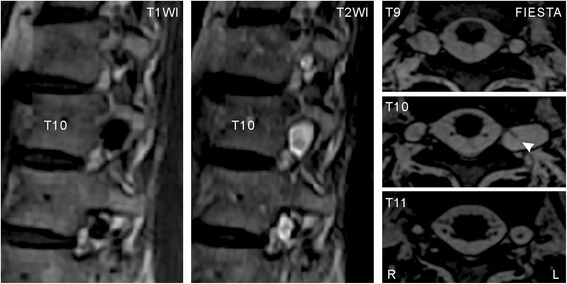

To identify the cause of the neuralgia, we performed MRI, which revealed multiple cysts at the T9–T11 nerve roots bilaterally (Fig. 1). No other causal abnormality for the chest wall pain was found other than the cysts. The interior of the cysts showed similar intensity to the CSF on imaging. The largest cyst was at the level of the left T10 vertebra and had a linear shadow that suggested the presence of nerve root fibers. Computed tomography (CT) with myelography was also performed to study CSF communication between the thecal sac and the cysts. After 10 mL of 240 mg I/mL iodinated contrast medium (Omnipaque 240, Daiichi Sankyo, Inc., Japan) was injected into the thecal sac at L4/5 in the lateral recumbent position, the first CT image was taken immediately (left and middle columns of Fig. 2), and revealed multiple cysts from T6–L2, including small cysts. The cysts were enhanced by the contrast medium and most showed the same intensity as that of the thecal sac at the corresponding level; however, the largest cyst at left T10 and another at left T9 showed much higher concentrations of the contrast medium. Three hours after the injection, the intensities of the cysts and the thecal sac were equal on the second CT (right column of Fig. 2). The next day, another CT examination showed no detectable contrast enhancement. Based on these findings, we suggested a diagnosis of multiple perineural cysts.

Magnetic resonance images at T9–T11 showing multiple perineural cysts. Sagittal views at the level of the left intervertebral foramina on T1- (left) and T2-weighted (middle) images show multiple cysts on the left side. In axial views acquired by fast imaging employing steady-state acquisition (FIESTA, right), a linear shadow (arrowhead) is seen in the largest cyst at left T10